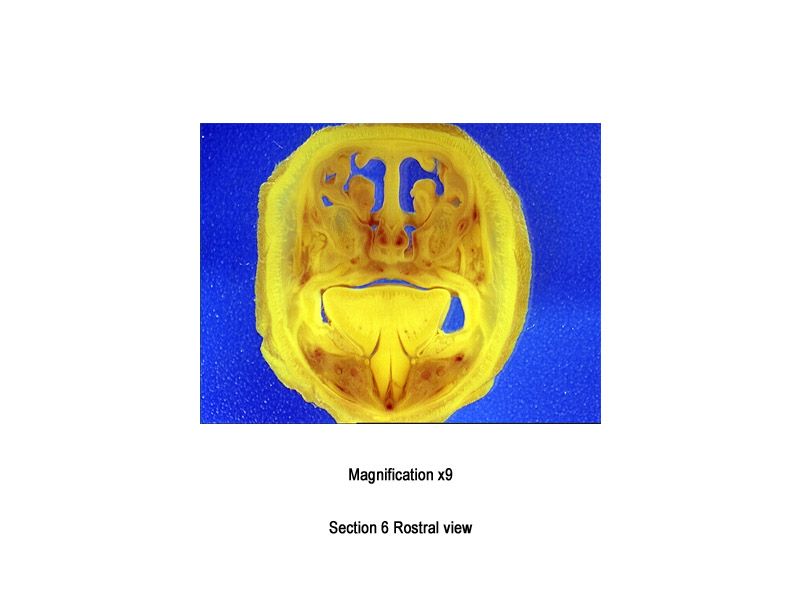

The images below show the normal appearance of Bouin's fluid fixed head sections in specimens at Day 29 of gestation (day mating observed = Day 0).

It is essential that both sides of each section is examined so that structures that exist is several sections can be visualised by the examiner in their mind as 3D.